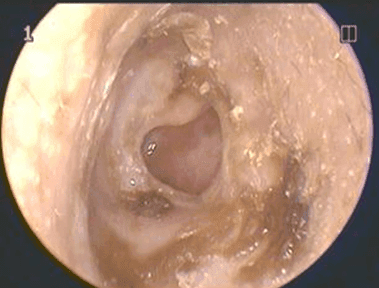

Kulak zarı delinmesinde tanı otoskop adı verilen cihaz ile kulak muayenesi sonucu klinik olarak konur. Bazen kulak zarının görülebilmesi için dış kulak yolundaki akıntıların temizlenmesi gerekebilir. Kendiliğinden kapanmış olan bir delik bazen çok ince bir zar şeklinde olabilir ve kulak zarı delikmiş gibi gözlenebilir. Özellikle ameliyat edilecek hastalarda işitme testleri yapılmalıdır. Görüntüleme yöntemleri ek bir sorun yoksa genellikle gerekmez.